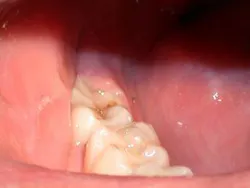

Often when a general dentist is restoring lower molars, an operculum can be found which can hinder his or her restorative endeavors (Fig. 1). The perfect tool for removing this operculum and assisting the dentist is the soft-tissue laser. The soft-tissue laser can remove the offending operculum atraumatically, often with little or no anesthesia and no postoperative discomfort or bleeding. Those who practice microdentistry with air abrasion or a hard-tissue laser can be particularly assisted by the durable hemostasis afforded by a soft-tissue laser. Those dentists who are familiar with hard-tissue lasers know that, although soft-tissue surgery is possible with the Erbium wavelengths, the hemostasis that is afforded can be negligible in all but the healthiest tissues. This is a fact that is supported by the physics of the wavelengths. The author, who is a lecturer for bioLitec is particularly excited by the excellent tissue effects, no charring and durable hemostasis, that are derived by the 980nm wavelength of the bioLitec SmilePro 980. This wavelength has the highest water absorption of all of the near-infrared wavelengths. Since tissue is comprised of nearly 60 to 80 percent water, water absorption is a valuable property in tissue-cutting lasers.